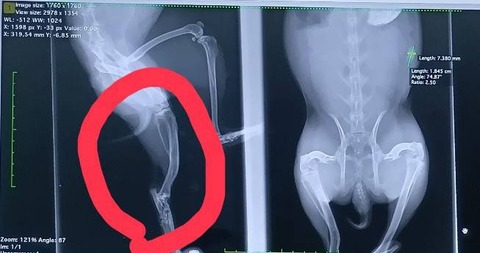

2025年11月に右後ろ脚を骨折し、11/14にピンニング手術を受け、現在も経過観察中です。

2/11 1800g 経過確認のため受診しました。

足裏の汚れは左右差はなく、足はよく使えており、ソアホックもありませんでした。

レントゲンでは骨の状態も良好で、筋肉もついてきており順調とのこと。

ここまで回復してくれたことに安堵しています。

ワイヤーが残ってるため、今後は先端が刺激になって炎症起こす可能性があり、

様子に変化があれば受診し、ワイヤー除去または先端を切る処置が必要になる可能性があると説明を受けました。

日常生活は通常通り可能とのことですが、様子を見ながら慎重に過ごしています。

次回再診は6月予定です。